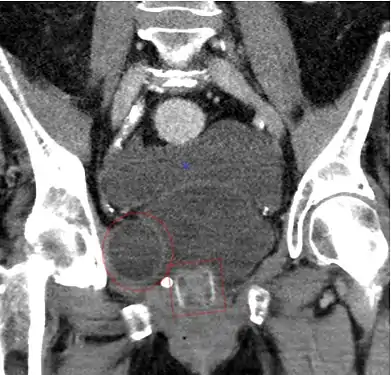

CT Scan (reconstruction coronal) montrant un AMS 800 chez une femme